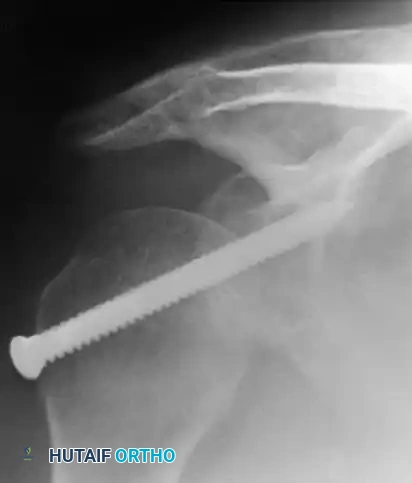

1. Transarticular Fixation:

Neviaser recommended transfixing the glenohumeral joint with a Swiss screw to provide rigid temporary stability.

Alternatively, Wilson and McKeever described the use of crossed Kirschner wires driven through the acromion directly into the humeral head.

If internal fixation (screws or K-wires) is utilized, the arm is supported in an abduction splint or spica cast, and the hardware is removed at 3 to 4 weeks in the clinic.

When the anteromedial humeral head defect is between 20% and 45%, it will engage the posterior glenoid rim, causing recurrent instability. McLaughlin described a technique to fill this defect by transferring the subscapularis tendon (with or without the lesser tuberosity) directly into the defect, effectively converting an intra-articular defect into an extra-articular one and preventing engagement.